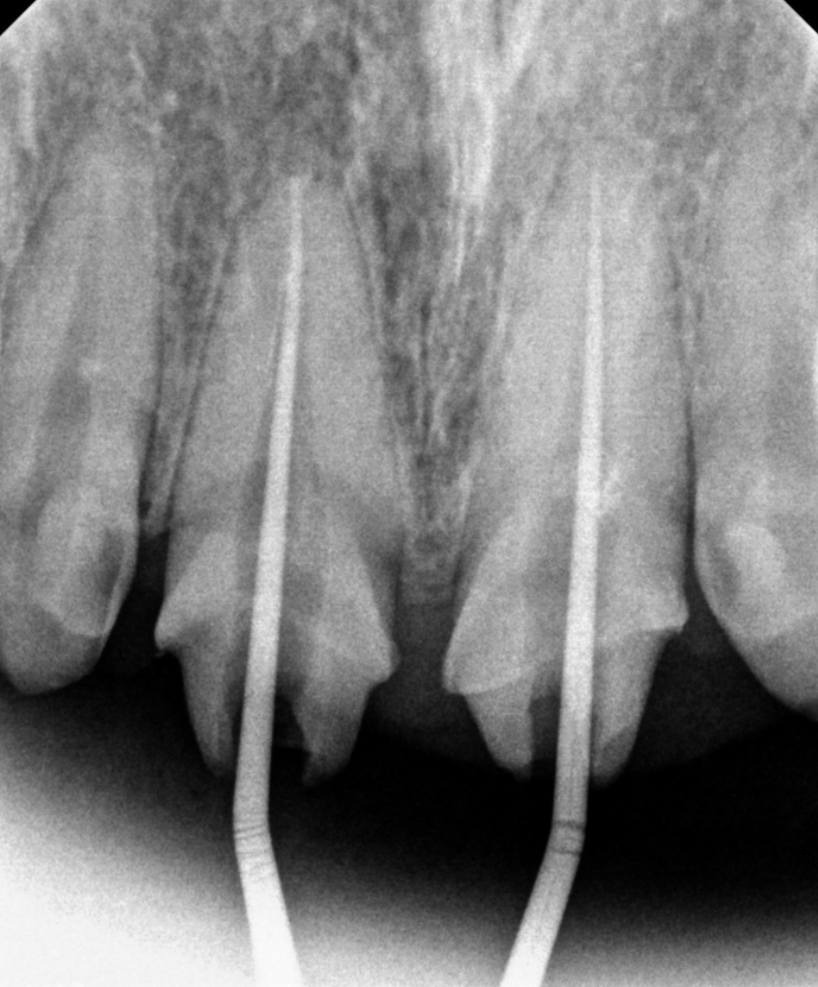

위쪽 앞니 보철물을 한지 오래됐는데, 바꾸고 싶어요. 안녕하세요. 주안역치과 365서울앞선치과 대표원장 강동우입니다. 오늘 소개해드릴 치료 증례는 앞니 보철물이 어색하다는 불편감으로 내원하신 환자분의 증례입니다~ 앞니는 치아의 기능도 중요하지만 무엇보다 심미성이 중요합니다. 쉽게 말해 앞니는 이쁜게 중요하다고 볼 수 있습니다 ㅎㅎ 촬영일시 : 2024.05.03. 처음 내원 당시 정면 모습입니다. 환자분께서 나이가 젊으셨음에도 불구하고 앞니의 보철물의 색상이 탁하고 어두워보이며 심지어 앞니 끝부분이 깨져있는것도 보입니다. 또한 PFM이라고 내부에 금속구조물을 포함한 보철물이다보니 금속 구조물이 빛의 투과를 막아 잇몸색이 탁한 색으로 보이는 우산효과(umbrella effect)도 관찰됩니다. 촬영일시 : 2024.05.03. 내원 당시 치료전 엑스레이입니다. PFM으로 제작된 앞니 보철물이 관찰되며, 치아 내부에 신경치료가 행해졌던 흔적도 보입니다. 환자분께서 증상은 따로 없으셨으나, 신경치료 상태가 불량하여 재신경치료도 진행하기로 했습니다. 촬영일시 : 2024.05.03. 재신경치료 중에 촬영한 엑스레이입니다. 정확하게 신경치료가 이루어지고있는것이 관찰됩니다. 촬영일시 : 2024.05.03. 재신경치료 후 엑스레이 사진입니다. 깔끔하게 충전된 양상이 관찰됩니다. 촬영일시 : 2024.05.03. / 2025.08.02. 이제 심미의 완성을 위한 잠정보철물(Provisional restoration)을 제작하여 환자분께서 원하는 형태를 찾아가며, 잇몸의 형태도 조절하는 과정(gingival molding)을 진행합니다. 환자분께서 심미를 중요시 여기는 분이셔서 두 번에 걸친 임시치아 제작 단계를 거쳐 최종적인 보철물을 만들었습니다. 촬영일시 : 2025.08.02. 완성된 최종보철물입니다. 깔끔하게 잘나왔습니다 어두웠던 잇몸색상도 개선되었습니다. 환자분께서도 만족하셨습니다 ㅎㅎ 촬영일시 : 2024.05.03. / 2025.08.02. 치료 전후 비교 모습입니다. 드라마틱한 변화가 관찰됩니다. 오늘은 오래된 앞니 보철물 교체에 관한 주제로 증례를 소개해드렸습니다. 앞으로도 좋은 치료로 보답하는 석바위시장치과, 365서울앞선치과가 되겠습니다 ! [ 치료기간: 2024년 5월3일 ~2025년 8월 2일 ] ※ 365서울앞선치과의원의 모든 포스팅은 각 진료과 의료진이 직접 작성합니다. 365서울앞선치과의원 블로그의 임상 케이스 게시물은 환자분께 의학적으로 정확하고 상세한 정보를 드리기 위해 각 진료과 의료진이 직접 작성하며, 모든 증례 사진은 본원 의료진이 직접 시술한 증례를 촬영한 것으로, 의료법 제23조, 제56조에 의거하며 환자분의 동의를 얻어 포스팅에 사용하였습니다. 또한 해당 케이스는 본 환자분의 치료 결과이며, 환자 상태에 따라 치료의 결과는 달라질 수 있습니다. |